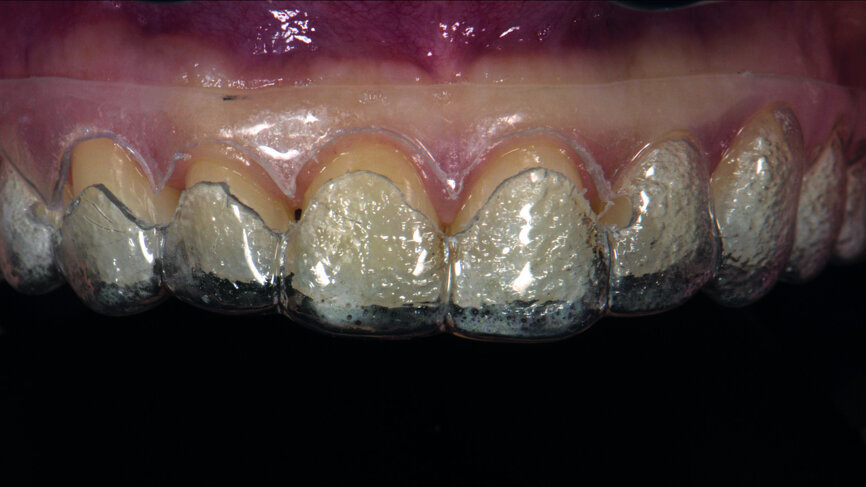

Fig. 16e: Veneers in situ before finishing and polishing procedures.

Fig. 16f: Final outcome immediately after removal of the rubber dam.